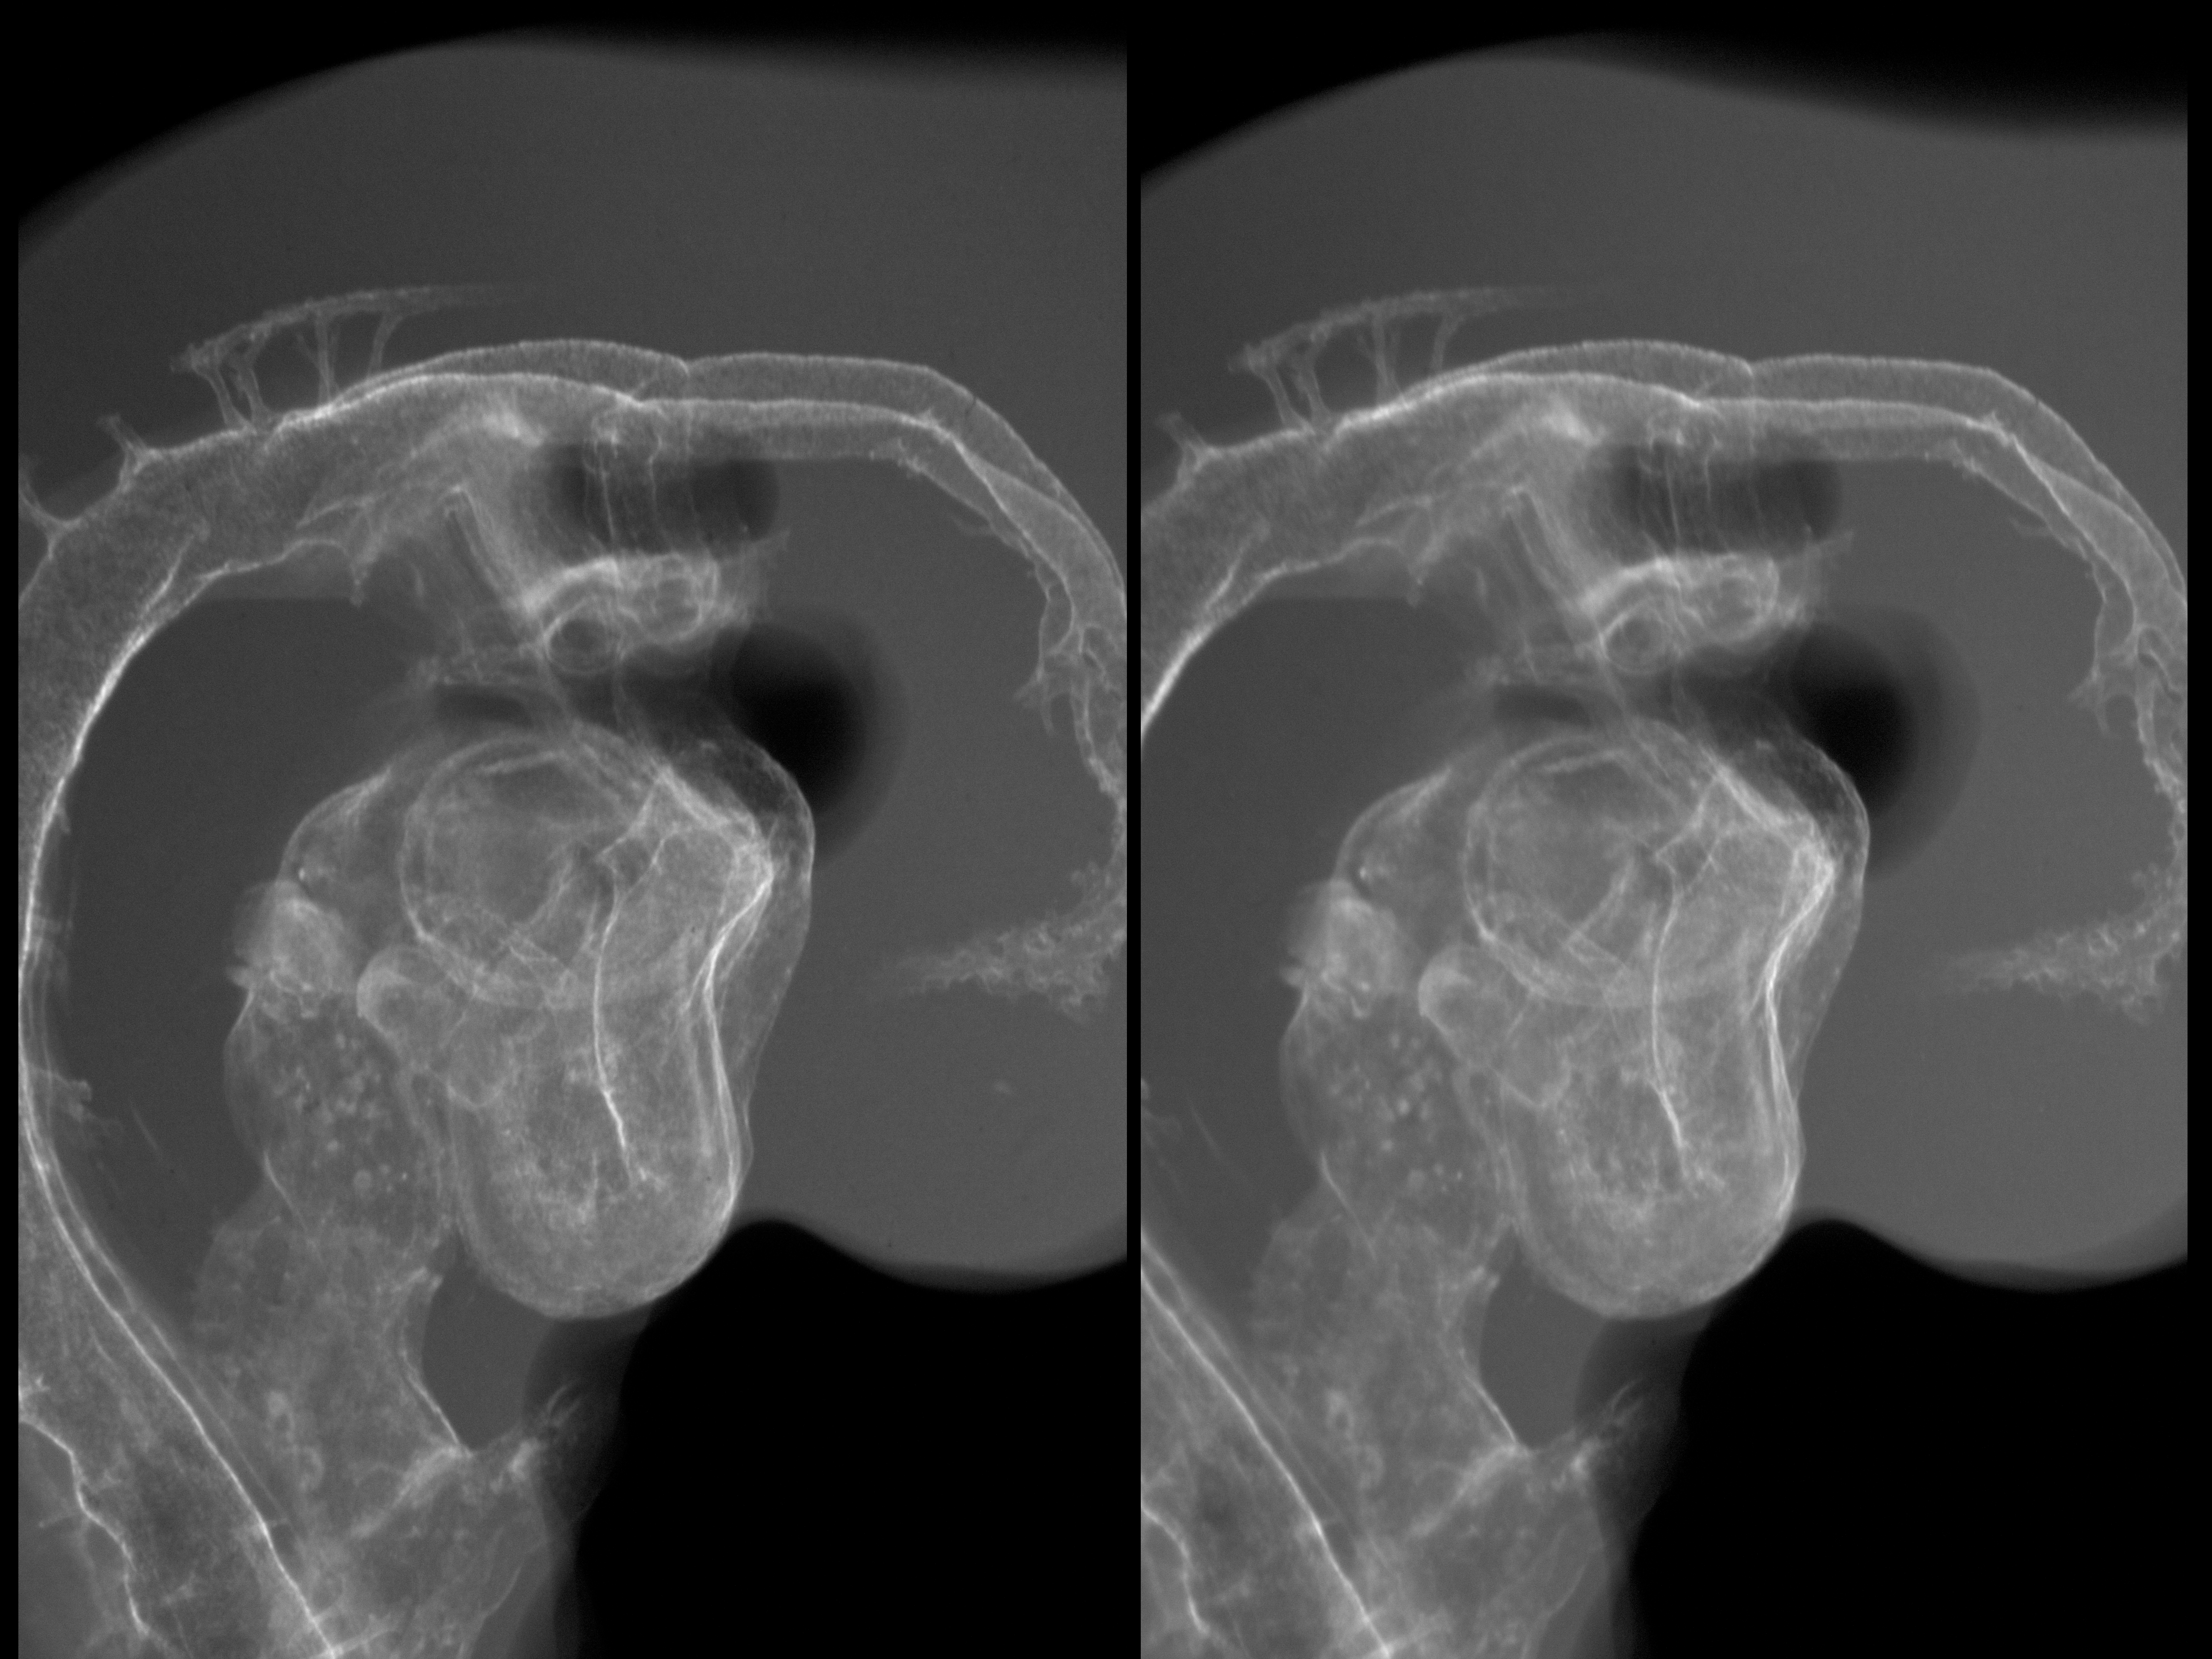

Chick Embryo Microangiography

Hamburger-Hamilton (HH) Stage 19 (approx. 3 - 3.5 days)

Stereo X-Ray Micrographs